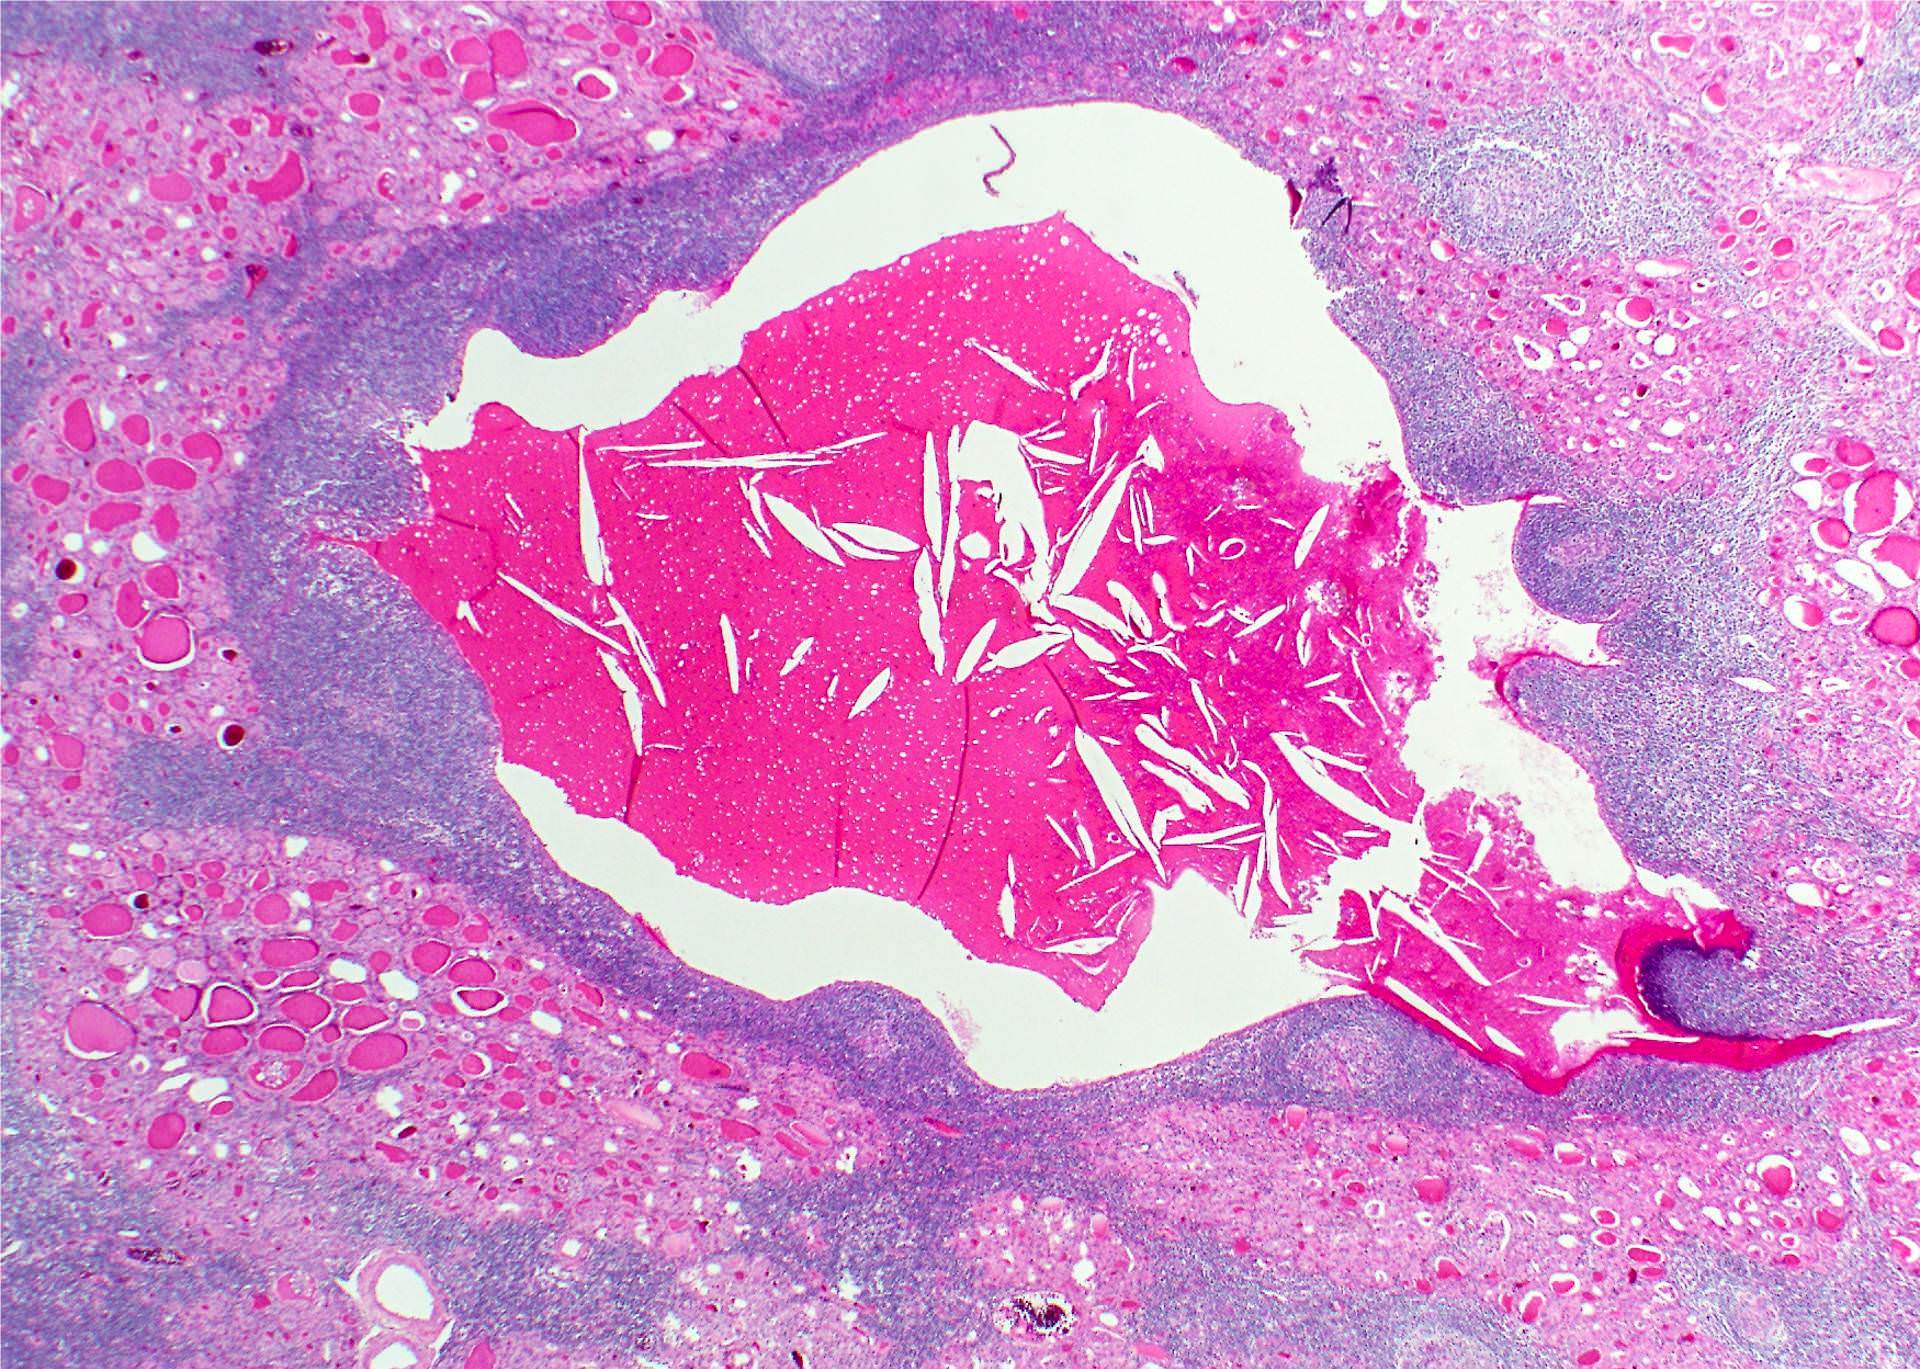

Microscopic (histologic) description

- Classic form: diffuse infiltration of thyroid parenchyma with lymphocytes and plasma cells; lymphoid follicle formation with germinal centers (Best Pract Res Clin Endocrinol Metab 2019;33:101367)

- Fibrous (or fibrosing) variant: extensive keloid-like fibrosis of thyroid parenchyma, fibrous septa divide the parenchyma into lobules, mononuclear cell infiltration, lymphoid follicles, thyroid follicular atrophy, oncocytic cell and squamous metaplasia (Autoimmun Rev 2014;13:391)

- IgG4 related variant: dense lymphoplasmacytic infiltrate, enriched in IgG4 producing plasma cells (> 20 cells per high power field); interstitial fibrosis; often associated with obliterative phlebitis (Autoimmun Rev 2014;13:391)

Microscopic (histologic) images

Contributed by Andrey Bychkov, M.D., Ph.D. and Shipra Agarwal, M.D.